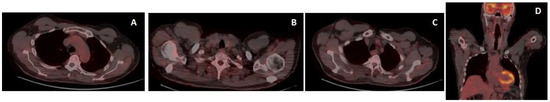

A bone marrow biopsy was performed, a diagnosis of stage-II NHL was made, and the patient underwent monoclonal antibody anti-CD30 Brentuximab Vedotin in association with CHP chemotherapy (Cyclophosfamide, Adriblastine, Prednisone) for six cycles from March to July 2022, with complete remission after three cycles (early PET). No particular signs of toxicity were observed during treatment, which was well-tolerated. The patient is on follow-up, with a good health condition and persistent complete remission, as confirmed by PET/CT restaging at the end of the treatment (Figure 6).

Figure 6.

Restaging 18-FDG-PET/CT after chemotherapy showed the complete metabolic response of all the involved sites (A–D).